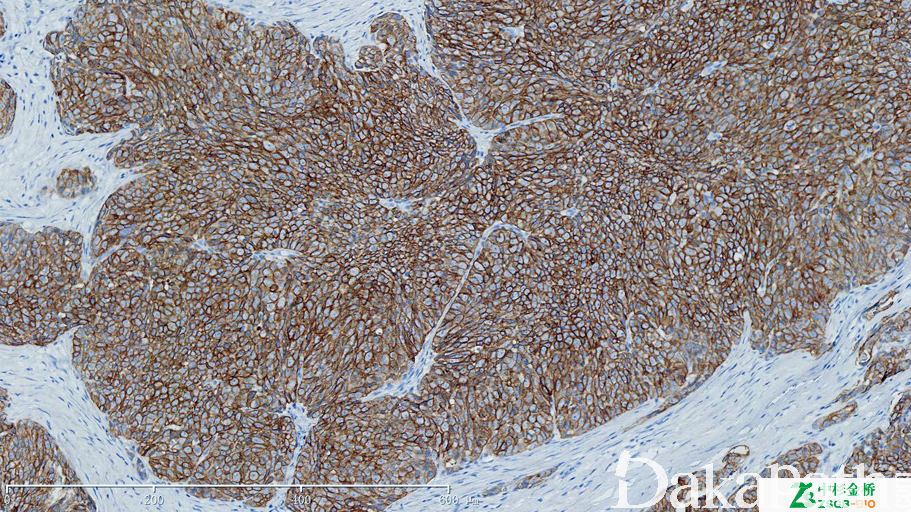

CK7

阳性:肺、乳腺、子宫内膜、甲状腺及卵巢的腺癌,移行细胞癌等, 需与 CK20 参照

信号定位: 胞质